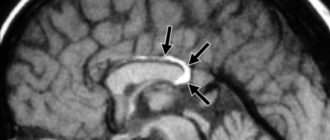

Липома мозолистого тела головного мозга 01 Август 0 просмотров 0 рейтинг Липома (более известна